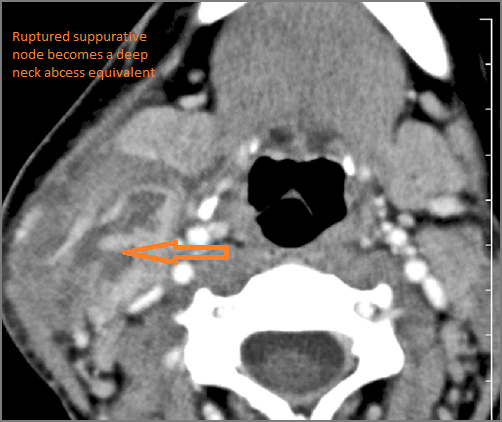

If there is suppurative cervical adenopathy the purulent material outside the lymph node(s) capsule(s).